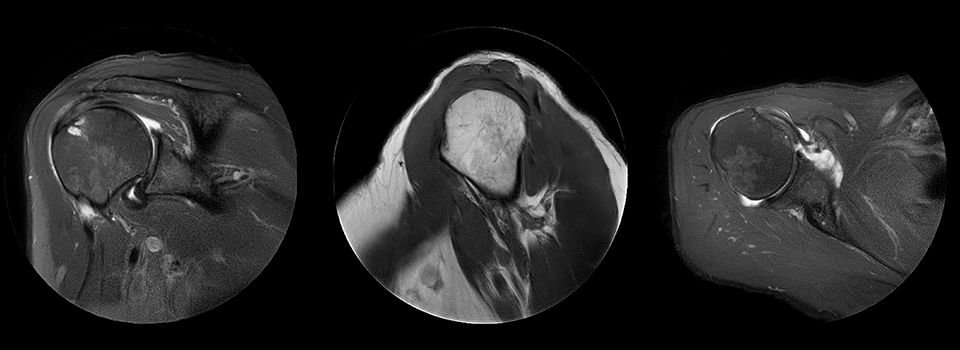

Shoulder with MultiVane motion reduction

MultiVane was used for motion reduction in this shoulder examination, providing excellent detail that is not obscured by motion artifacts, as happens quite commonly when no proper motion reduction method is available. Images from Ingenia Ambition.

MCVI Ambition shoulder with multivane complete

Cor T2W fatsat

Scan time 3:06 min

Voxels 0.5 x 0.5 x 3 mm, recon 0.4 x 0.4

Sag T1W

Scan time 4:10 min

Ax PD fatsat

Scan time 4:17 min